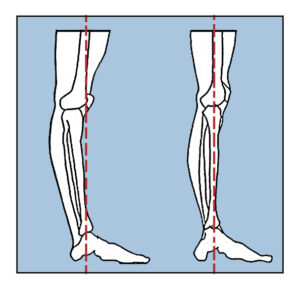

One of the most overlooked aspects of spinal health is the relationship between leg alignment and pelvic stability.

Getting the legs directly under the pelvis is essential to creating a stable foundation that allows the spine to find its natural curves without strain.

Many people, including but not limited to people with scoliosis, develop compensatory patterns where they shift their weight unevenly, creating a chain reaction up through the pelvis and into the spine.

When the legs are properly positioned beneath the pelvis, they allow the bones to hold us up (which is their job) effectively transferring weight up and down the skeleton, reducing the burden on the spinal muscles and allowing for better overall alignment.

Hyperextension of the knees in hypermobility is common (my story), and this knee-locking tendency creates a rigid support system that can force the spine to compensate with increased curvature.

When someone habitually locks their knees, they’re essentially turning their legs into rigid posts rather than dynamic, responsive supports.

For hypermobile individuals, the instinct might be to create stability through rigidity – locking joints to feel secure. However, this strategy backfires by creating tension patterns that travel up the kinetic chain.

Instead of locking the knees, the goal should be to find active, engaged support through proper muscular coordination while maintaining joint mobility.

Learning to stand by positioning the legs beneath the pelvis, unlocking the knees (which is not something everyone does but if you do…), allowing the bones to stack, and lengthening the spine upward, becomes a lifelong practice that helps us to age more successfully..